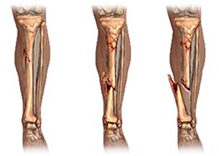

Per frattura si intende la condizione patologica in cui viene a crearsi una soluzione di continuità di un osso (ossia quando “l’osso si rompe”).

Se in una frattura i due monconi ossei non si spostano e mantengono, quindi, l’asse anatomico originale, si parla di frattura composta. Solitamente le fratture composte hanno una adeguata stabilità intrinseca che ne garantisce una buona guarigione; esse verranno trattate, pertanto, conservativamente, ovvero con un semplice gesso o tutore esterno.

Nel caso in cui la frattura determina lo spostamento dei due (o più) frammenti ossei, si parla di frattura scomposta. In questo caso si renderà necessaria una manovra di riduzione che ristabilire i corretti rapporti anatomici.

La manovra riduttiva, applicando una trazione manuale sul segmento fratturato, permetterà il corretto allineamento dell’osso. Se tale manovra non risulta efficace o qualora la frattura risulta instabile nonostante l’immobilizzazione con gessi o tutori, si renderà necessario un intervento chirurgico per riallineare la frattura e renderla stabile.